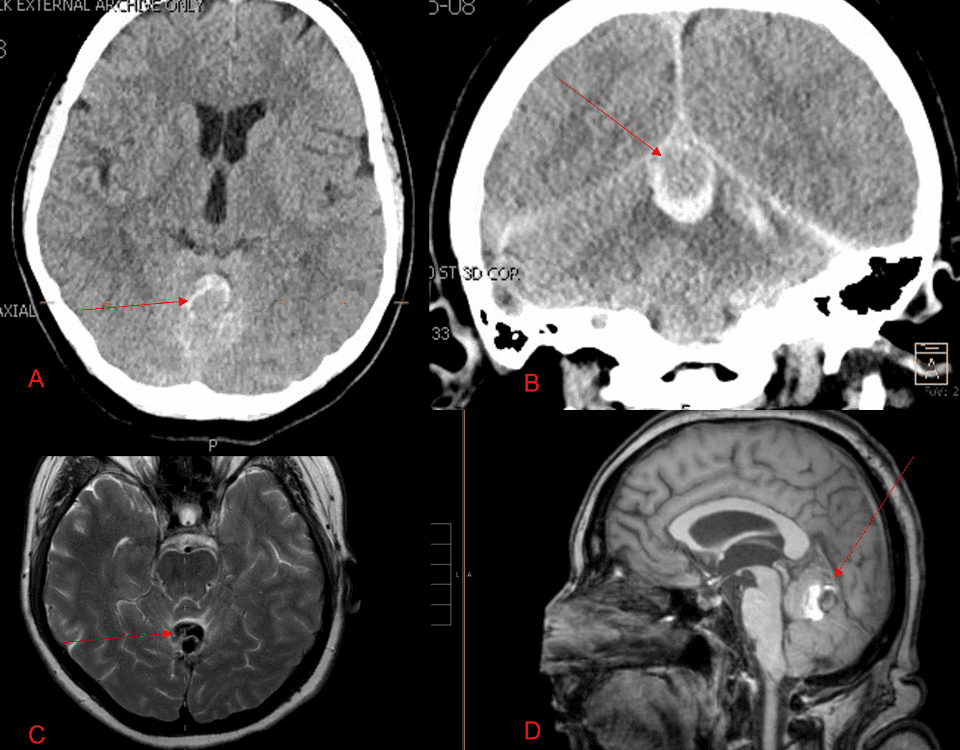

Case Presentation: A woman in her 80s developed mild dizziness and headache following incidental trauma working in her garage one day. She presented several weeks later […]